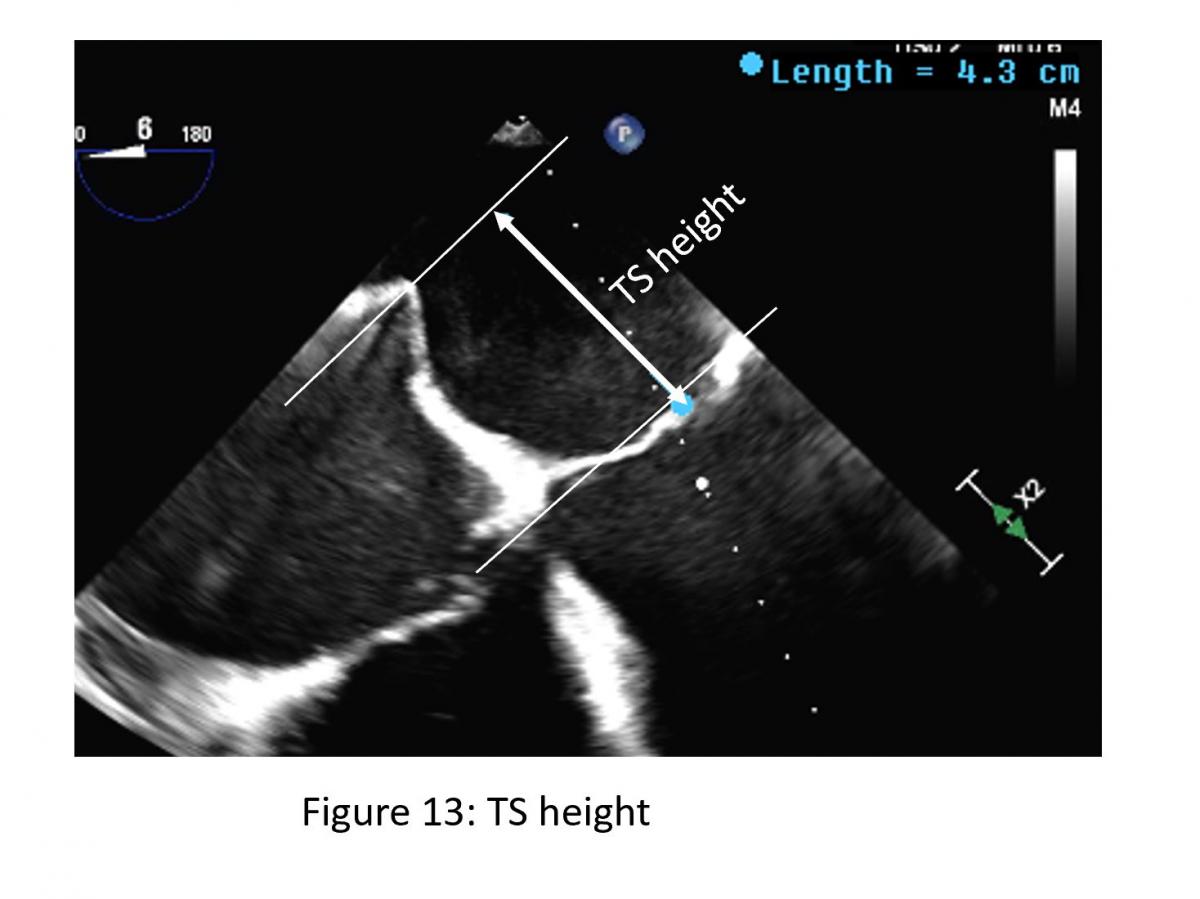

Figure 13: 4-chamber TEE view from transeptal height (TS)

The site of optimal transseptal puncture is slightly different for PMR and FMR. In structural mitral leaflet disease (e. g. prolapse or flail), the puncture site needs to be 4–5 cm above the mitral annulus to guarantee enough space for adequate catheter and MitraClip maneuvering. In contrast, in cases of functional MR, the line of coaptation is usually below the plane of the mitral annulus due to extensive tethering. Therefore, the puncture site in these patients needs to be more inferior and closer to the annular plane (about 3.5-4.5 cm above the annular plane). Also, a different location of a lesion that cause MR may also require adjustment of septal puncture site (Figure 13).

TS height

• Primary MR 4.0-5.0 cm

• Functional MR with apical tethering of mitral valve leaflets 3.5 -4.5 cm

• Flail - higher

• Lateral (A1/P1) – lower

• Medial (A3/P3) – higher